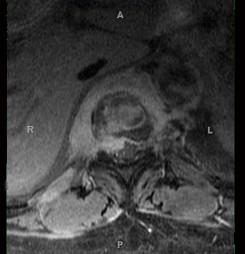

问题 女,67岁,突发右侧背痛半月余,请结合影像学检查,选择最可能的诊断 ( )

选项 A、脊椎结核 B、强直性脊柱炎 C、椎体压缩骨折 D、脊柱转移瘤 E、化脓性脊柱炎

答案 A